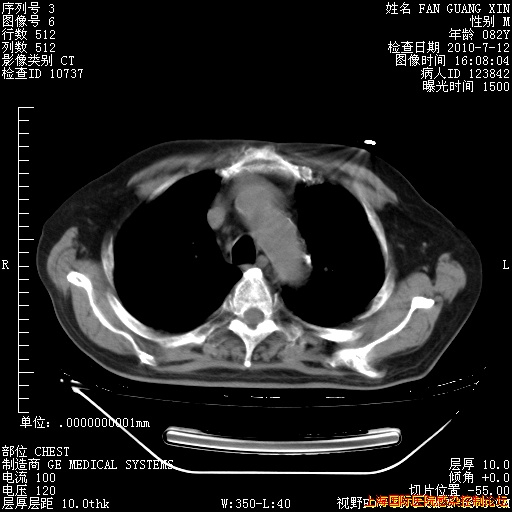

6月12日纵膈窗

回复